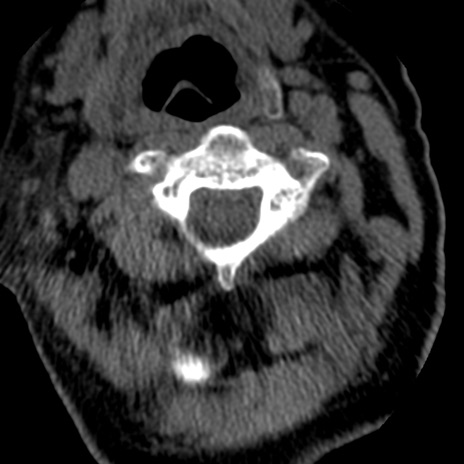

症例50 頚椎CT(横断像)

頚椎CT